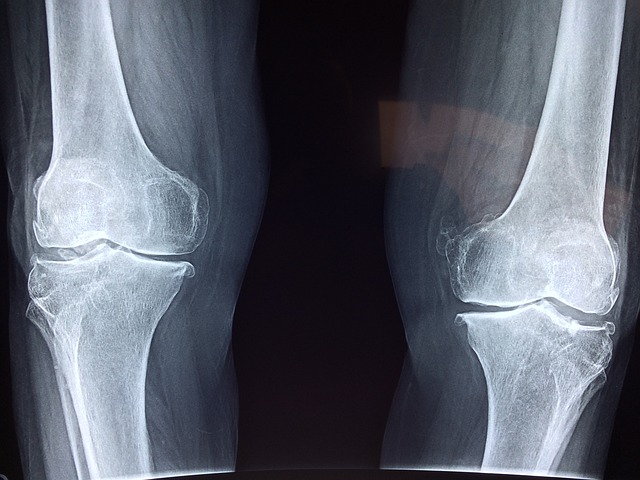

• 방사선 검사 : 엑스레이, MRI 등을 통해 관절 손상 여부 확인 가능

| 구 분 | 류마티스 관절염 | 퇴행성 관절염 |

| 원인 | 면역 체계 이상 | 연골 마모 |

| 증상 | 양측 대칭적 통증, 손목, 발가락 영향 |

특정 관절 통증, 소가락 끝 주로 영향 |

| 아침에 뻣뻣함 | 30분 이상 지속 | 짧거나 없음 |

| 진행 속도 | 급성 또는 서서히 진행 | 점진적 진행 |

| 치료 접근 | 면역 억제제 사용 | 생활 습관 및 물리치료 |